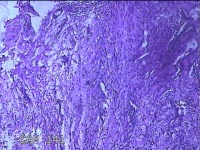

左侧卵巢囊肿⑴

性别

女

年龄

34岁

临床诊断

左侧卵巢子宫内膜异位囊肿

一般病史

下腹痛3小时入院。

标本名称

大体所见

灰白暗红色囊性肿物8x2.5x0.7cm一个,表面糜烂,部分已切开,囊内容物已流失,囊壁厚0.1cm。

图1